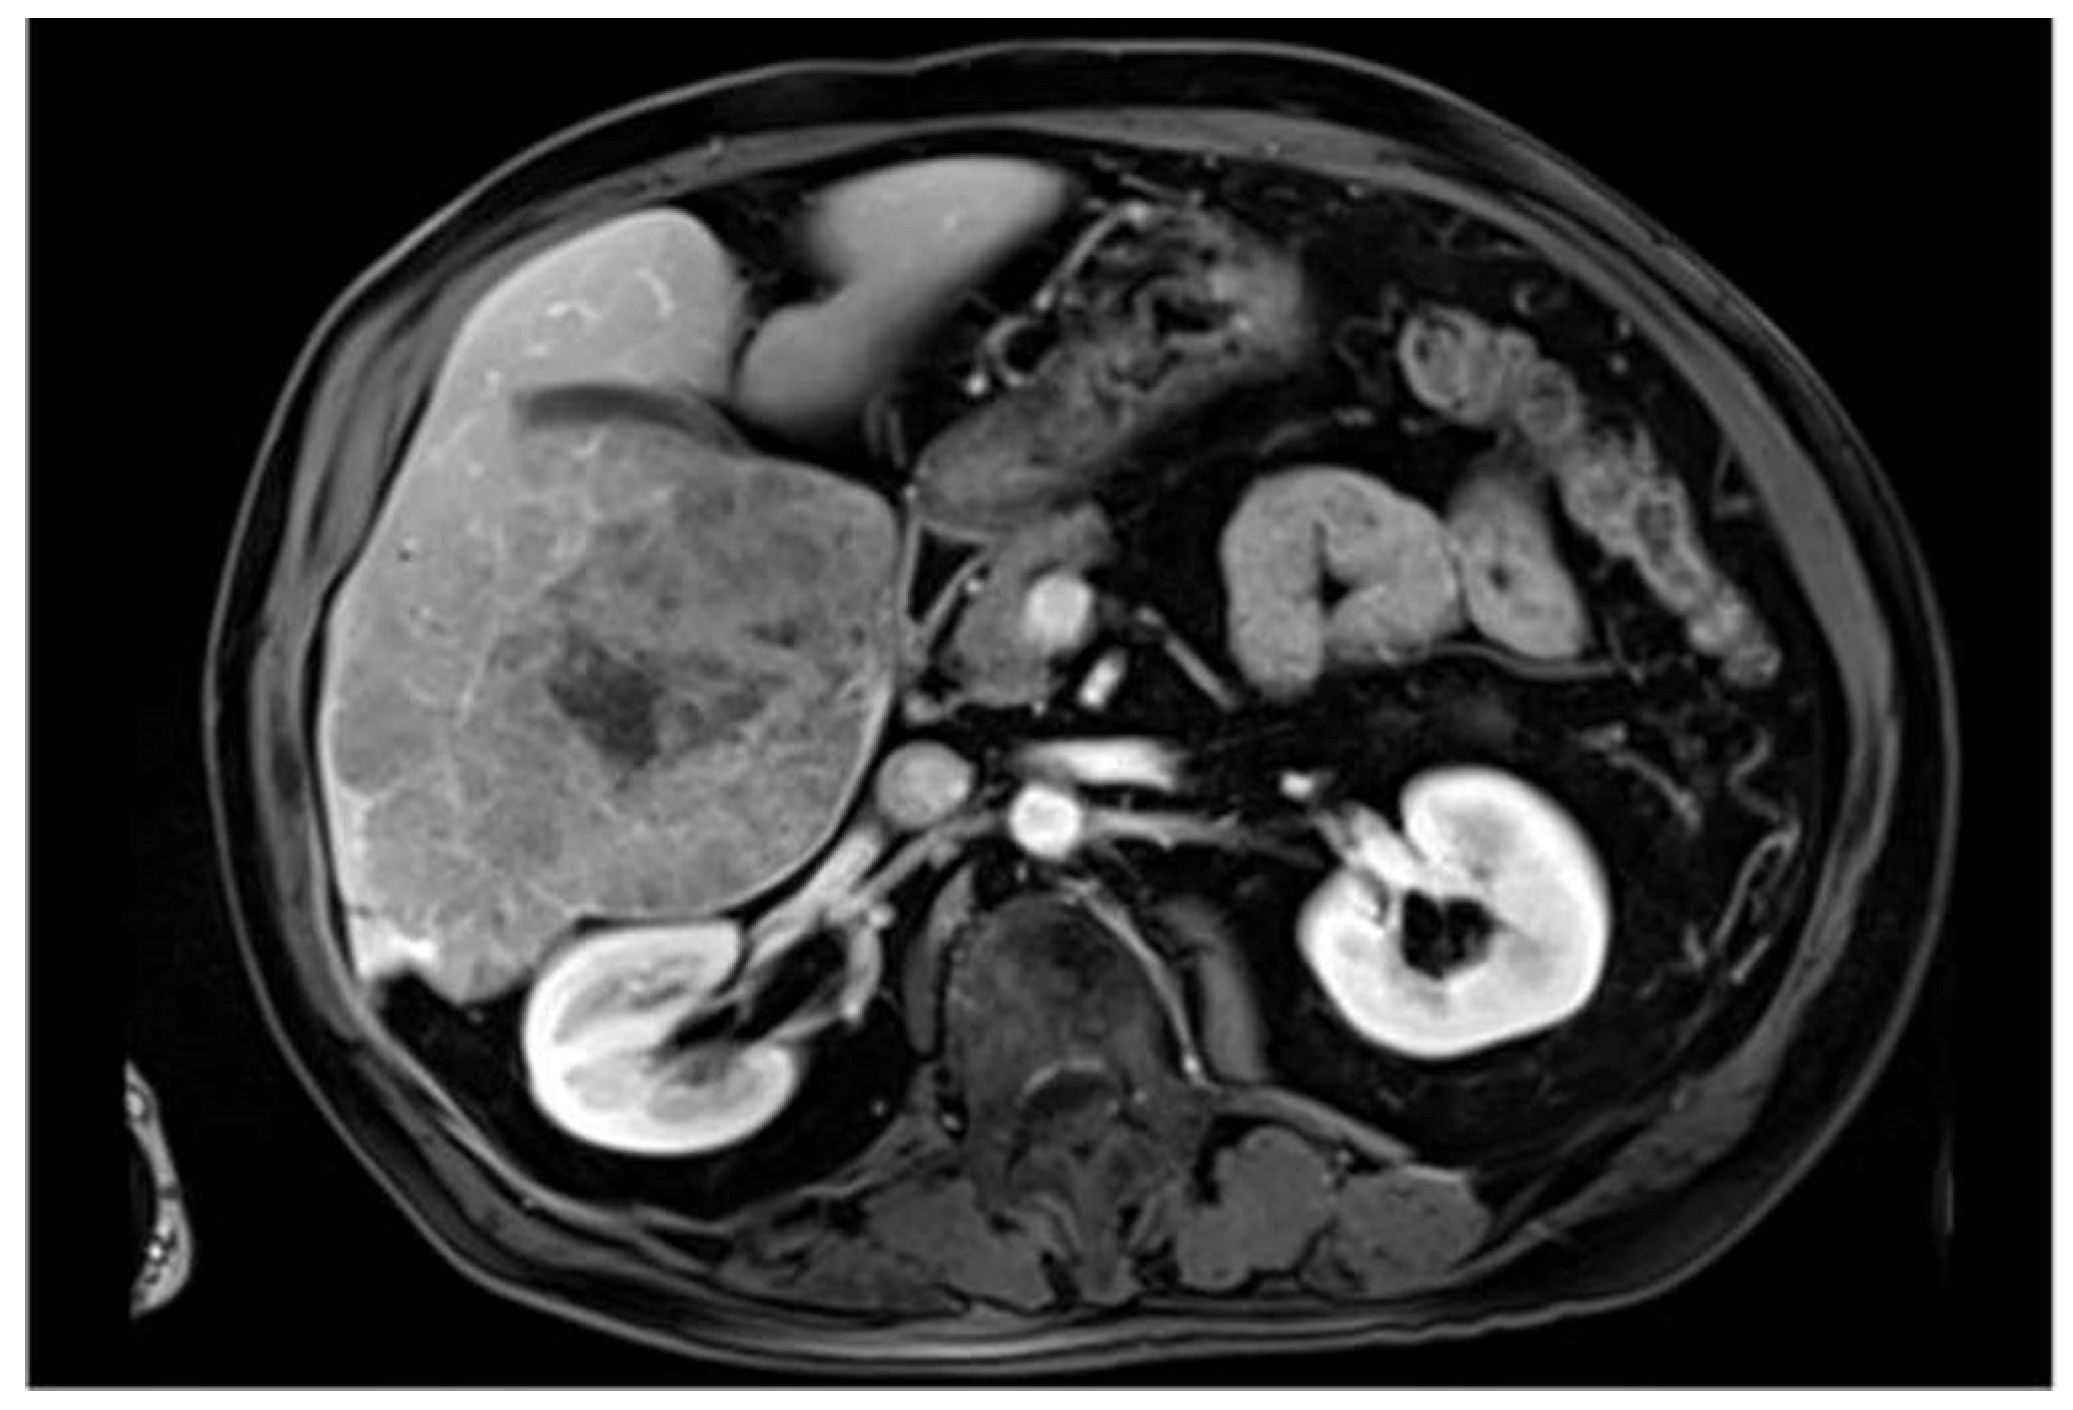

| ATLAS | Annotated CE-MRI data, particularly for inoperable HCC | First dataset of its kind, suitable for the optimization of contouring in liver cancer treatment planning | Newer datasets requiring validation of compatibility for widespread use |